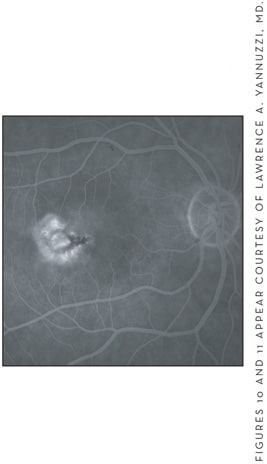

Early in the disease, FA shows mild, diffuse intraretinal leakage or staining. In more advanced cases, fluorescein leakage is evident in the superficial circulation, with cascades over the deep capillary leakage (Figures 10 and 11). OCT reveals retinal thickening and an inner lamellar cyst may be observed in cases of segmental or sectoral dilation overlying the dilated deep retinal telangiectatic vessels.33

Figure 10. Diffuse intraretinal leakage in the early phase of the fluorescein angiography (left).

Figure 11. Increase of the leakage in the late phase of the fluorescein angiography study (right).